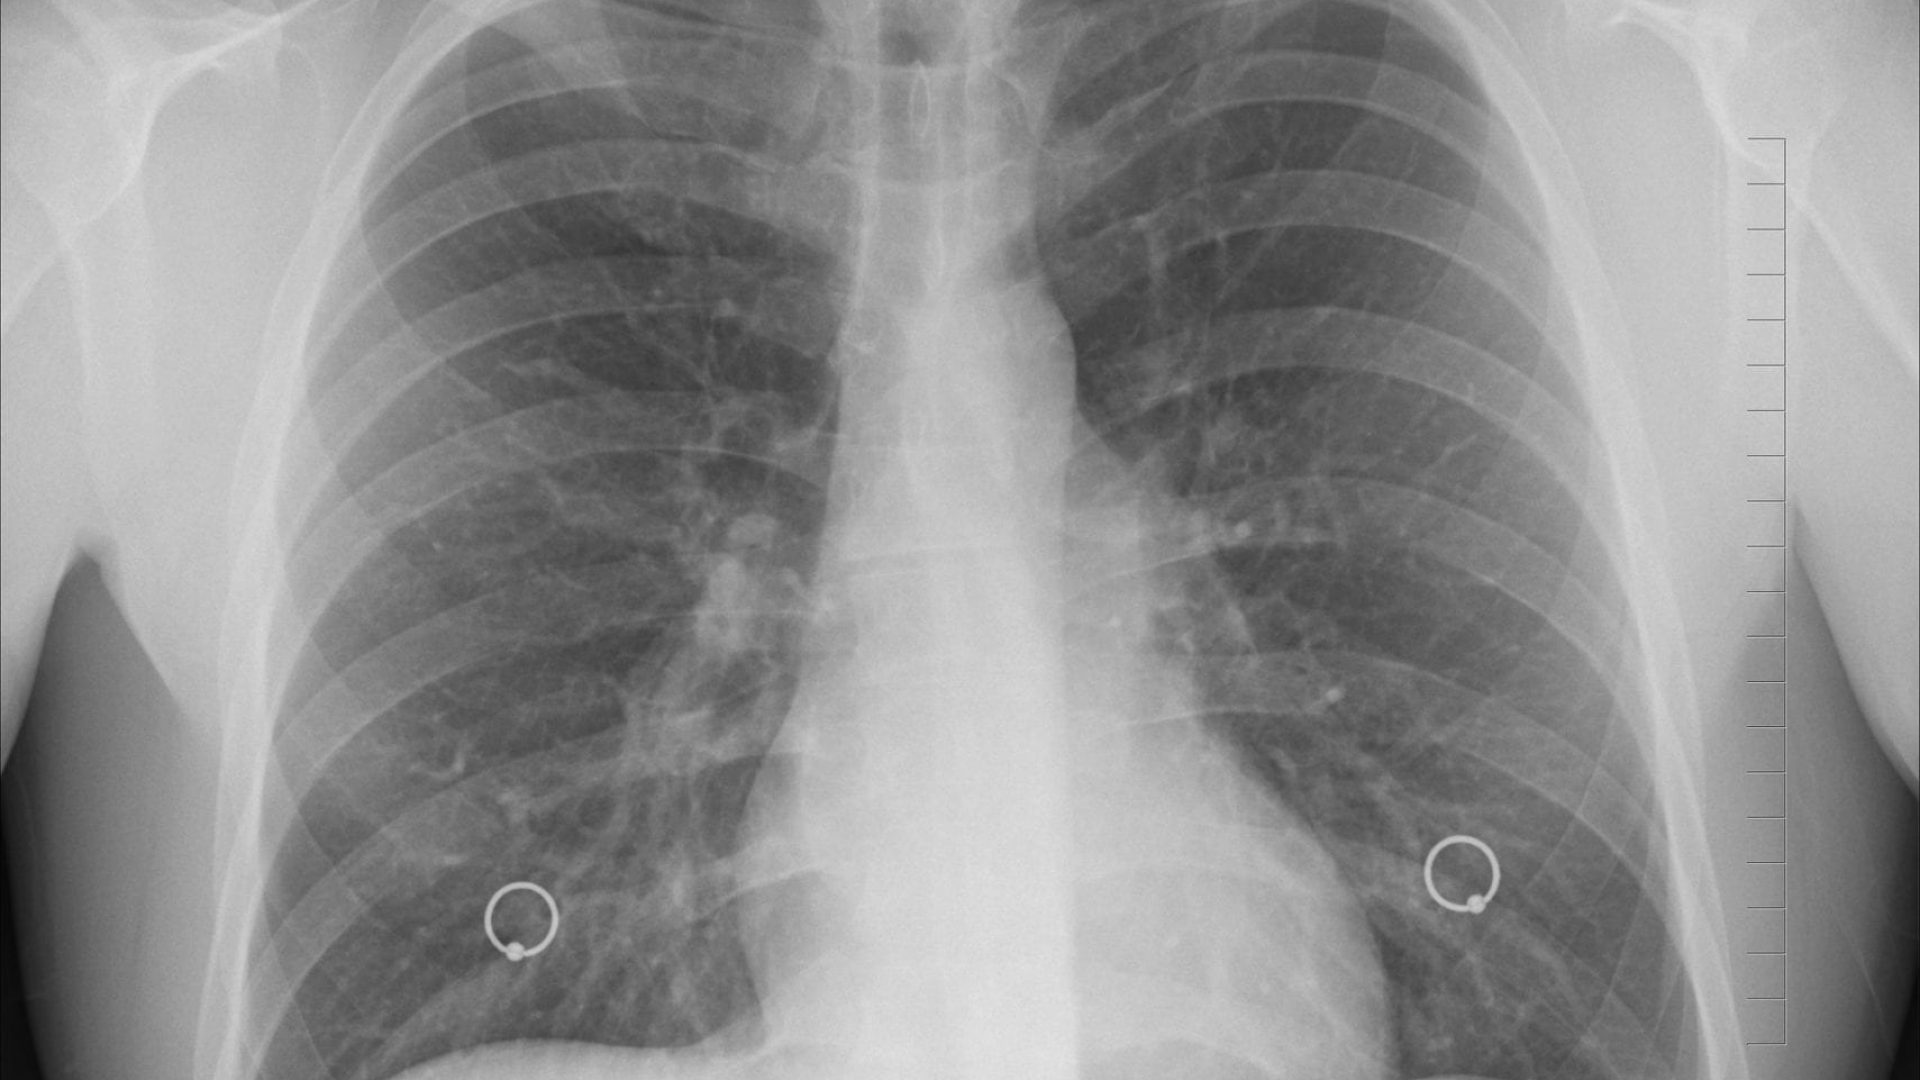

REVUE DE PRESSE – « Les centres américains de contrôle et de prévention des maladies viennent de publier des chiffres qui suscitent d’ores et déjà une grande inquiétude chez les dentistes et autres personnels liées aux soins bucco-dentaires. Un rapport fait en effet état d’un nombre anormalement élevé de fibroses pulmonaires idiopathiques chez les personnes ayant travaillé dans des cabinets de soin dentaire. »